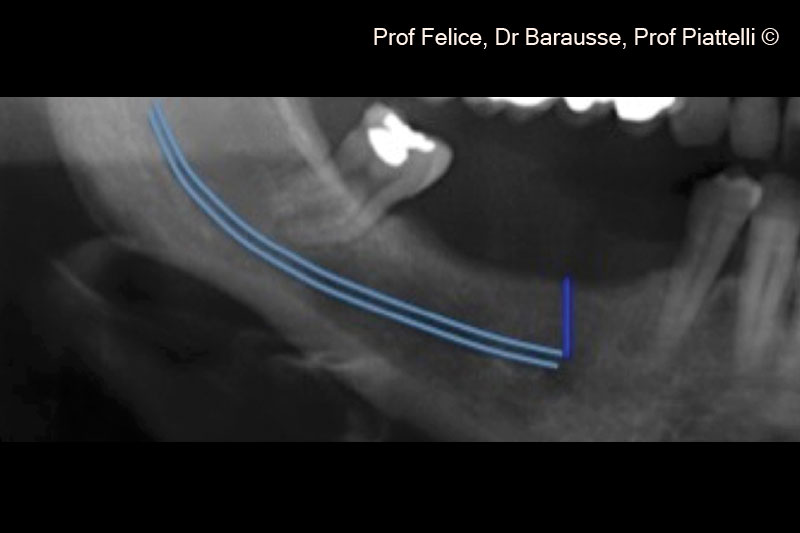

Một bệnh nhân nữ (70 tuổi) có biểu hiện teo xương hàm dưới bên phải phía sau.